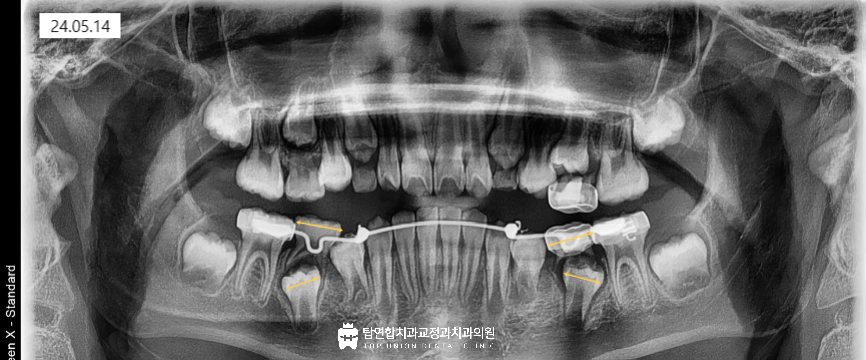

공간 유지 장치를 이용하여 전체 치열의 안정성을 확보하고

작은 어금니 부근에 훅(hook)을 추가로 디자인해서

원심으로 기울어진 제1소구치를 직립시키는 계획을 세웠습니다.

구강 내의 인상을 채득하여 모델을 제작한 뒤

계획한 치료에 맞는 공간유지장치+훅 장치를 제작하였습니다.

구강 내에 적용한 모습입니다.

훅에 탄성이 있는 파워 체인을 연결하여

반대 방향으로 당기는 힘을 주는 치료를 진행하였습니다.